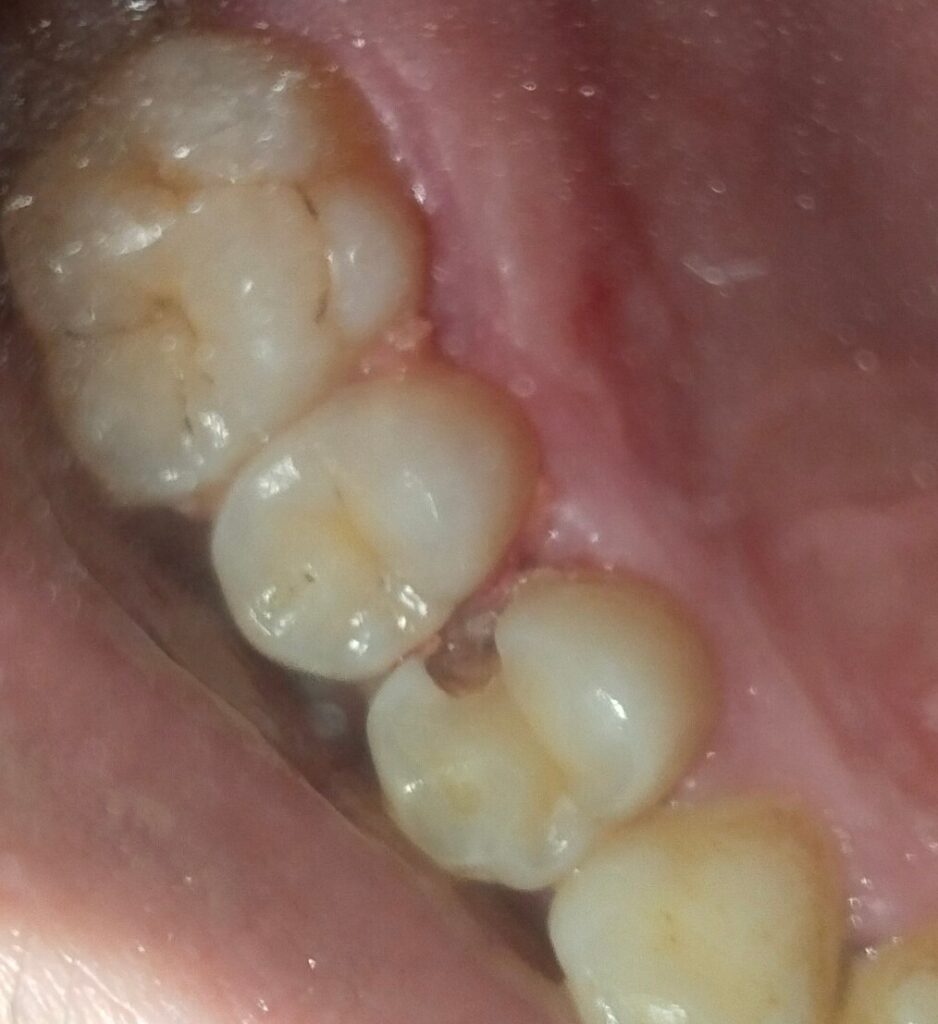

During his visit to Pakistan, Rahim faced sharp pain while eating, leading him to my clinic. Despite his fear of Root Canal Treatment, a thorough examination revealed that treating his upper right first premolar tooth with RCT was essential for pain relief and tooth preservation.

Utilizing rotary endodontics, we performed the RCT on Rahim’s upper right first premolar, known for often having two canals. In Rahim’s case, we confirmed the presence of two canals—the buccal canal measuring 21mm and the palatal canal measuring 22mm. Despite the complexity, the advanced techniques ensured precise treatment and Rahim’s comfort.